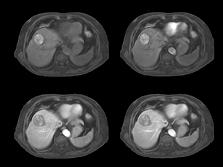

With 4D FreeBreathing, you can now offer free-breathing MRI liver to a broader population, while improving imaging confidence and the patient experience. This allows you to address patients who have difficulty holding their breath or find it difficult to follow breathing instructions.

4D FreeBreathing – Dynamic 3D T1w TFE Resolution: 1.6 X 1.6 X 5.0 mm Scan time: 3:16min Magnet ic Resonance